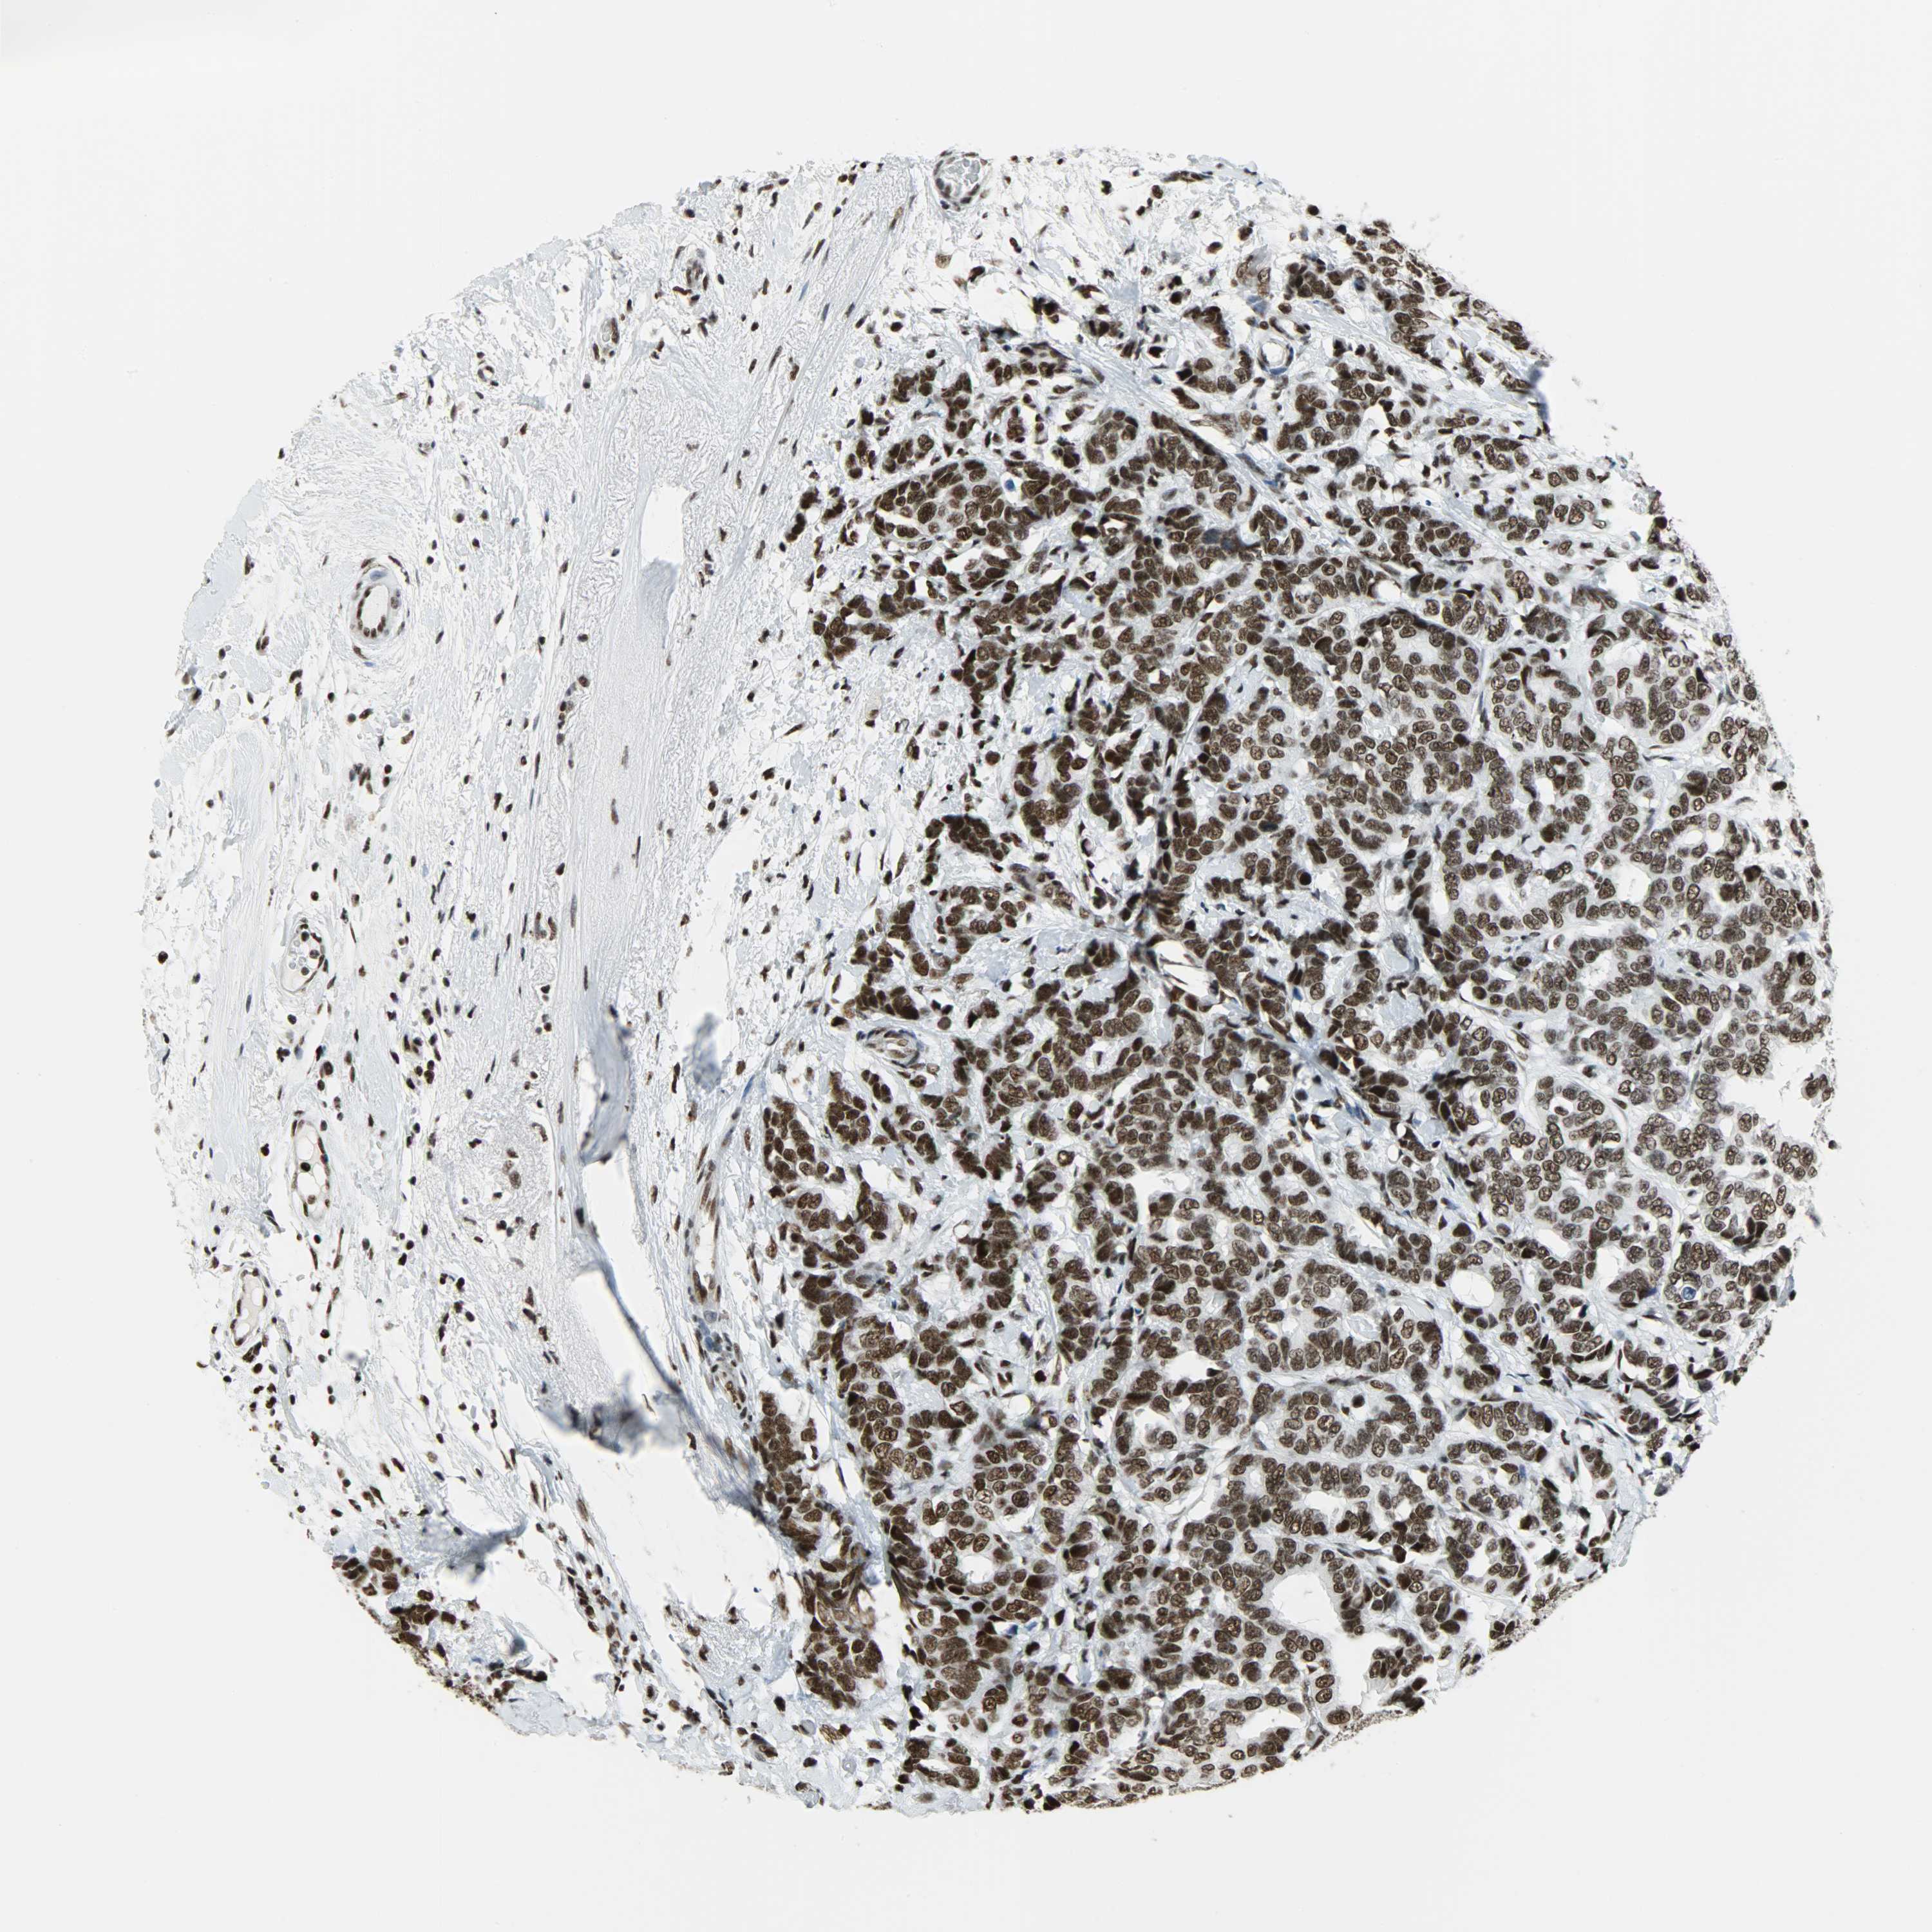

CANCER BREAST CANCER Show tissue menu

BRCA TCGA BRCA VALIDATION PROTEIN EXPRESSION

Breast cancer

Human cancer